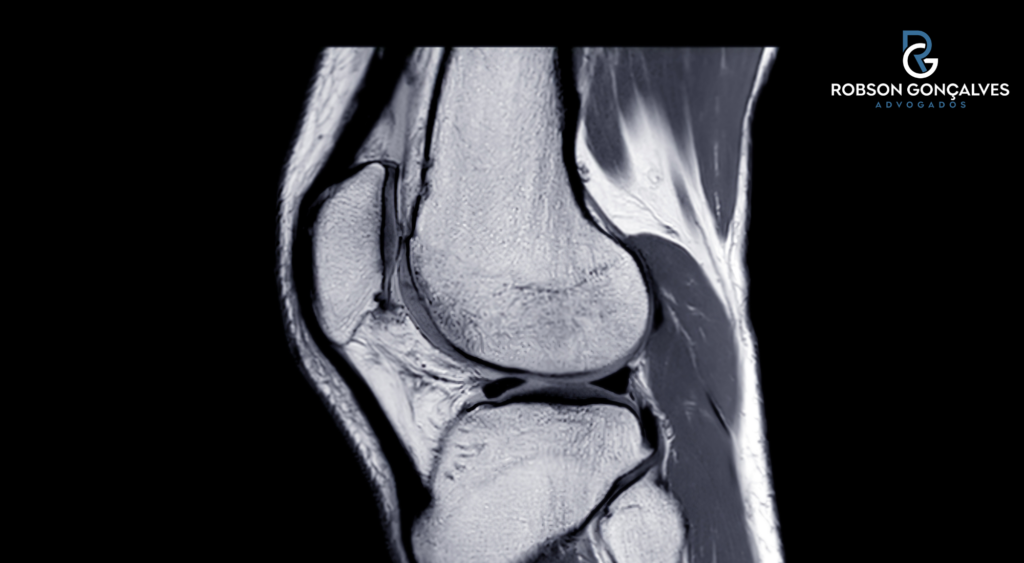

- ressonância magnética;

O ligamento cruzado anterior é uma das estruturas que estabilizam o joelho.

Em termos simples, ele ajuda a controlar movimentos de rotação e deslocamento da perna.

Quando ocorre a ruptura do LCA, parcial ou total, o joelho pode perder firmeza e passar a “falsear”, especialmente em atividades com giro, mudança rápida de direção, terreno irregular, subida, descida e esforço físico maior.